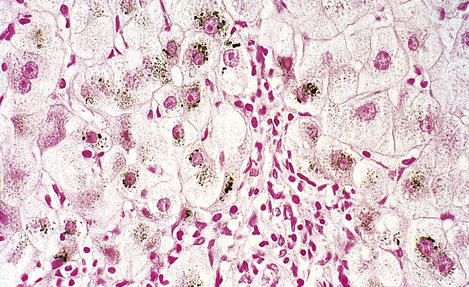

Wilson’s disease is the most important disorder of copper metabolism. This is inherited as an autosomal recessive condition in which copper accumulates in the liver (Fig. 7.10), basal ganglia of the brain, kidneys and eyes. The brown ring of copper deposition around the corneal limbus—the Kayser–Fleischer ring—is absolutely diagnostic. Serum caeruloplasmin levels are usually low. In the liver, the copper accumulation is associated with chronic hepatitis, frequently culminating in cirrhosis (Ch. 16). The neurological changes are seriously disabling. Although Wilson’s disease is rare, it is absolutely vital to consider the diagnosis in any patient presenting with chronic liver disease and neurological signs. d-Penicillamine, a chelating agent, has revolutionised the treatment of Wilson’s disease, but it is to little avail if the liver and brain have already been irreversibly damaged.

image

Fig. 7.10 Copper in liver. Liver biopsy, stained for copper (dark granules), showing excessive copper in periportal liver cells. No stainable copper would be present in a normal liver. Copper accumulates in the liver in Wilson’s disease and in patients with chronic obstructive jaundice (e.g. primary biliary cirrhosis).